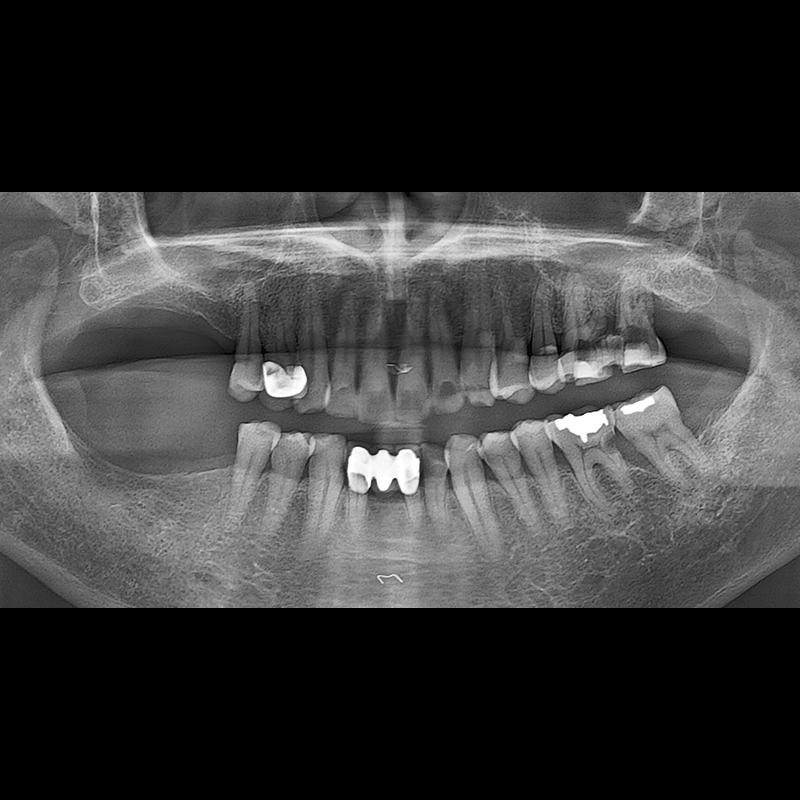

IMPLANT

BEFORE AFTER